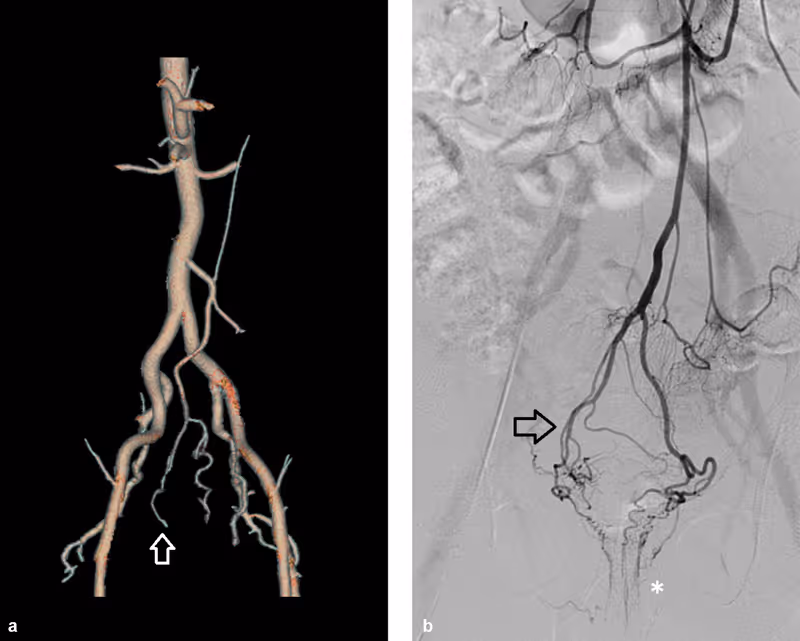

3. Hemorrhoidal Artery Embolisation (HAE)

Also known as ‘Emborrhoid Technique’, HAE is a minimally invasive radiological procedure that cuts off the blood supply feeding the hemorrhoids.

How It Works